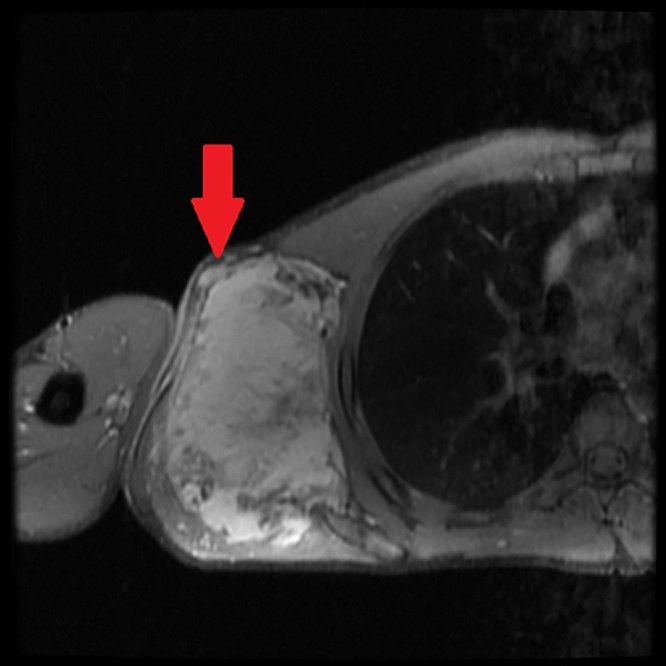

A 27-year-old male came to our hospital with complaints of a swelling in the right axilla for 2 and ½ years. It was insidious in onset and progressive in nature. The patient denied any history of pain, trauma, fever or weight loss. On examination, the swelling measured 12 cm × 10 cm, extending to the lateral border of the right scapula posteriorly, to the chest wall medially, to the apex of the axilla superiorly and to the 6th intercostal space inferiorly (Fig. 1). There was no warmth or tenderness noted. Skin over the swelling was normal and the surface was nodular. Dilated blood vessels were present over the surface of the swelling (Fig. 2). There were no visible pulsations, no discharge and no scars or sinuses. Movement of the shoulder joint was normal. The swelling was hard in consistency and not mobile. There were no palpable axillary or cervical lymph nodes. Baseline blood investigations were normal. Chest X-ray was normal and showed no osteolytic lesions of the right ribs or scapula (Fig. 3). Magnetic Resonance Imaging was done and showed an irregular mass in the right axilla in the muscular- subcutaneous plane measuring 10.8 × 8.8 × 12 cm. This mass was attached to the lateral border of scapula (Fig. 4) and displaced the subscapularis anteriorly. The infraspinatus, teres minor and teres major muscles were displaced posteriorly (Fig. 5). The lesion appeared iso to hyperintense to muscle on T1 and heterogeneously hyperintense on T2-weighted images. Multiple scattered areas of hemorrhage were noted within. The neurovascular bundle was seen displaced cranially. The lesion abutted the median, radial, ulnar nerves and axillary vessels in few sections. The lesion abutted the serratus anterior on the medial aspect.

Fig. 5.

MRI showing an irregular mass displacing infraspinatus, teres minor, and teres major muscles posteriorly. Multiple, scattered areas of hemorrhage noted within.